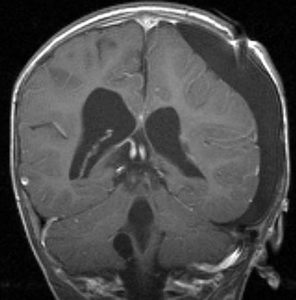

脳ドックなどでたくさん発見されるものです。両側に見られることが多いです。この患者さんは右側脳室の脈絡叢乳頭腫と診断されて来院されました。でも両側脳室三角部の脈絡叢のう胞です。右はガドリニウム増強ですが造影されません。これは経過観察の必要もなく放置してよいものです。

1歳児の巨大な脈絡叢乳頭腫です。このくらいのサイズになると手術で出血死することもあります。右側の画像は手術後のMRIで幸い全摘出できています。乳幼児のこのように巨大なものでは無理して全摘出にいどまないで,シャントをして水頭症を改善して,化学療法で腫瘍を小さくしてから,開頭手術するという方法もあるでしょう。執刀医の経験値で判断は異なります。